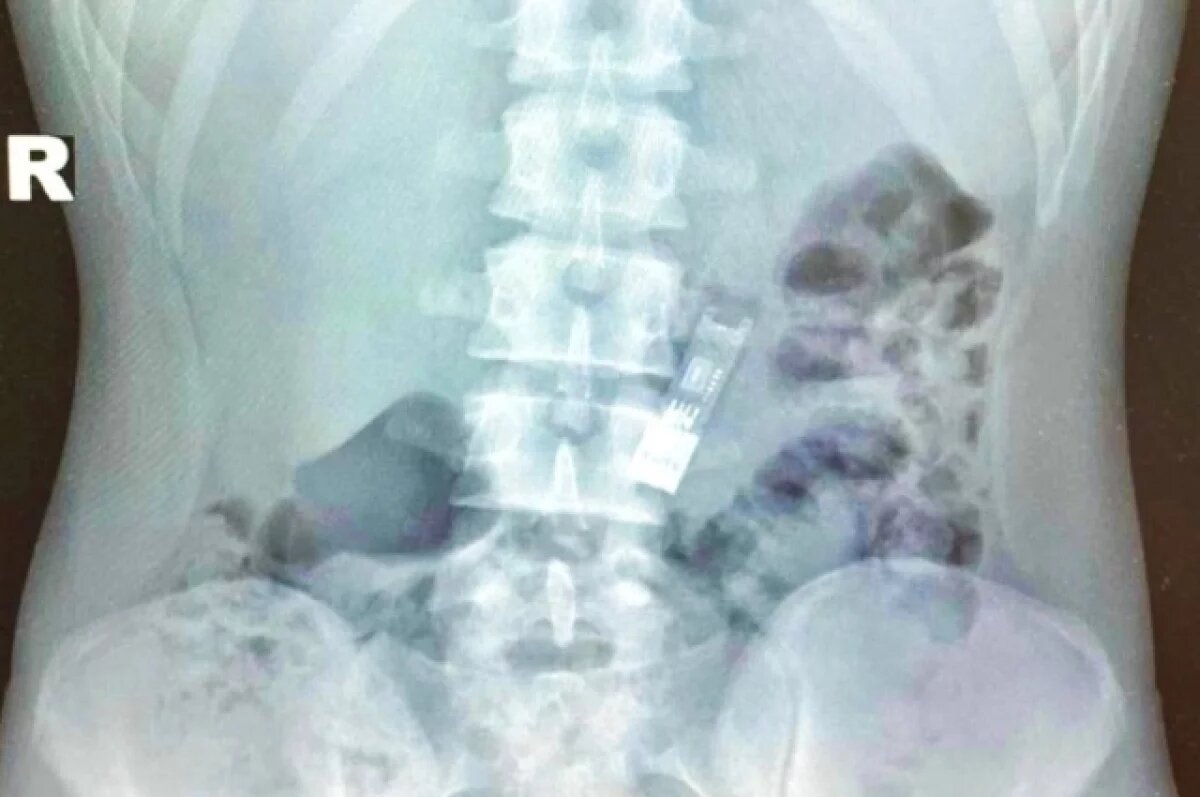

В Подмосковье медики извлекли из желудка 16-летнего школьника флешку с домашним заданием, сообщает пресс-служба регионального Минздрава. По информации министерства, подросток, выполнив домашнее задание по информатике и загрузив его на флешку, стал крутить ею перед лицом и случайно проглотил. «Иногда инородные тела выходят естественным путем, на что мальчик надеялся, но в данном случае этого не произошло», - говорится в публикации. Сообщается, что родители школьника привезли его в Детский клинический центр имени Л. М. Рошаля. Там инородный предмет достали из желудка подростка при помощи эндоскопических щипцов. Манипуляция была проведена под наркозом. В министерстве отметили, что флешка не причинила вреда организму школьника. Загруженное на нее домашнее задание также не пострадало. Ученик успешно сдал его. Ранее сообщалось об извлечении подмосковными медиками зубной щетки из желудка 16-летней девушки. Больше срочных и эксклюзивных новостей — в телеграм-канале АиФ

Сообщается, что родители школьника привезли его в Детский клинический центр имени Л. М. Рошаля. Там инородный предмет достали из желудка подростка при помощи эндоскопических щипцов. Манипуляция была проведена под наркозом.